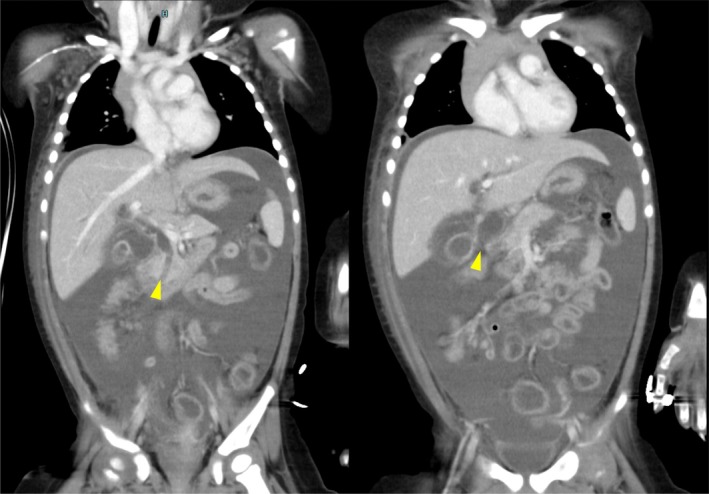

A 13‐month‐old female, weighing 11 kg, presented with abdominal pain and vomiting. The medical history of the patient was unremarkable. She was initially admitted to a local hospital with suspected acetonemic vomiting. Her symptoms worsened over 3 days, leading to abdominal guarding. Contrast‐enhanced computed tomography (CT) revealed massive ascites, dilation of the intrahepatic and extrahepatic bile ducts, and a 19 mm‐long common channel containing a hyperdense structure suggestive of a protein plug (Figure 1). A diagnosis of CBD (Todani classification type IV‐A) with bile duct perforation was made, and the patient was referred to our hospital for surgical intervention.